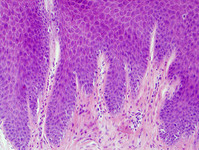

High-power photomicrograph of lichen simplex chronicus (haematoxylin-eosin stain, x200)

From the personal collection of Dr Brian L. Swick; used with permission